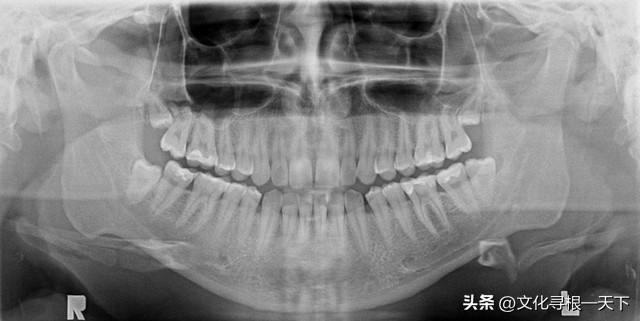

其实,我的牙齿原本洁白无瑕,上牙16颗,下牙16颗,智齿、臼齿、犬齿、切齿,32个弟兄对应整齐,酸甜苦辣咸,软硬弹缠粘,吃吃喝喝,无坚不摧,全怨头脑总司令遇事不公,为了满足味觉的需要过量食用糖果;为了满足双手懒惰的需要而忽视刷牙,同是一家弟兄,顾此失彼,这样娇惯了其它肢体而伤害了牙齿,使他藏污纳垢,身体透支,以至实施绝地报复,造成整体痛苦,既后悔又愧疚,深感对不起牙齿。

第一次先到修复科做修复前的检查。牙医是个40多岁的中年女士,态度很好,笑眯眯地在我口腔里检查了一下,开单子去放射科拍片子,然后说: